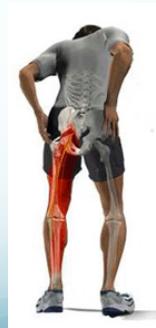

Clinical Picture

- Demographics: Male adults (35-50y) commonly affected

- Onset: Sudden backache while lifting or bending forwards

- Symptoms:

- Back pain and sciatica (increased with straining and coughing)

- Numbness and paresthesia

- Motor weakness

Detailed Clinical Features by Herniation Level

| Level of Herniation | Pain Distribution | Numbness Area | Weakness Pattern | Atrophy | Reflex Changes |

|---|---|---|---|---|---|

| L4–5 disc; 5th lumbar nerve root | Sacroiliac joint, hip, lateral thigh and leg | Lateral leg, first 3 toes | Dorsiflexion of great toe and foot; difficulty walking on heels; foot drop may occur | Minor | Internal hamstring reflex diminished or absent |

| L5–S1 disc; 1st sacral nerve root | Sacroiliac joint, hip, posterolateral thigh and leg to heel | Back of calf, lateral heel, foot to toe | Plantar flexion of foot and great toe may be affected; difficulty walking on toes | Gastrocnemius and soleus | Ankle jerk diminished or absent |

| L4-L5 disc (L5 root) | Over sacroiliac joint, hip, lateral thigh and leg | Lateral leg and first 3 toes (L5 dermatome) | Dorsiflexion of great toe and foot | Minor | Internal hamstring reflex diminished/absent |

| L5-S1 disc (S1 root) | Over sacroiliac joint, hip, posterolateral thigh and leg to heel | Back of calf, heel, foot to toe (S1 dermatome) | Plantar flexion of foot and great toe | Gastrocnemius and soleus muscles | Ankle jerk reflex changes |